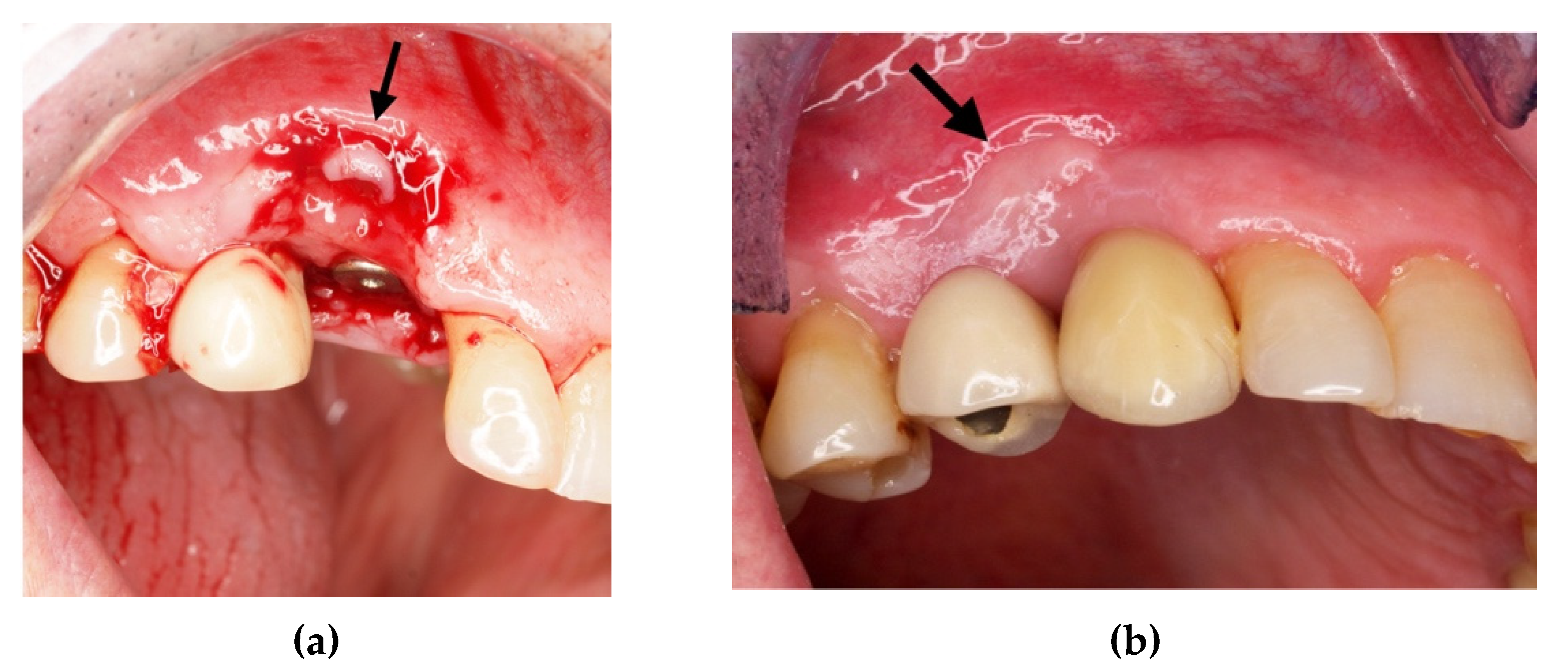

3. Clot Management and Titanium Foil: Biological Principles

4.1. Clinical Case n.1.

4.2. Clinical Case n.2.